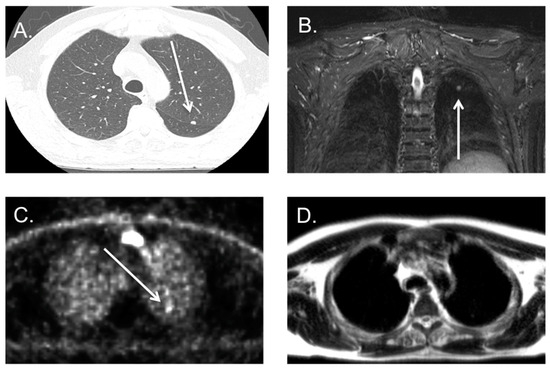

3.3. Indeterminate Lung Nodule Detection

3.4. Lung Metastases